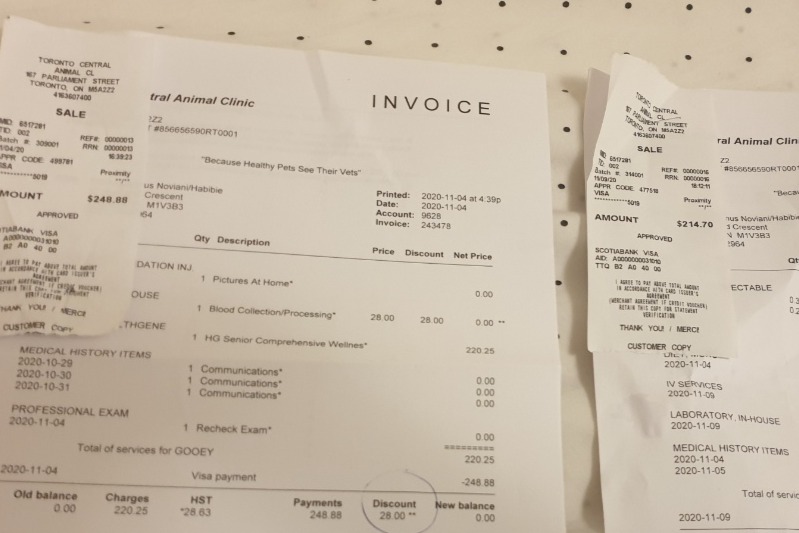

Gooey, Male.Gooey has been my best friend for 4 years, I got him since he was still a 3.5mths puppy, I brought him with me on the plane from Indonesia. While it is also the first time with me arriving in Canada. We going through a lot of difficulties together, while this pandemic also make everything more difficult for us. Right now his vet bills totalled $3401.

I have peoples donated to me directly totalled $1120. So I just need a little bit more kindness from all of you, please.

4 Nov - Gooey is back at the vet to take another blood test. And I discussed a lot of things with the doctor, its going to be quite long story.